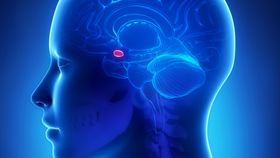

The rest of this article is behind a paywall. Please sign in or subscribe to access the full content.The amygdala plays an important role in emotions, aggression, and sexual arousal. The last of these in particular has raised suspicions that if any part of the human brain might vary between men and women, this would be it. This certainly seems to be the case in rats. When early MRI studies reported that men had larger amygdalae than women, it was enough to see the claim reported in books and popular science articles.

Science is constantly evolving, however. Dr Lise Eliot of Rosalind Franklin University of Medicine and Science decided to look more closely at the expanded MRI data. Using 46 published studies measuring the sizes of healthy male and female amygdalae (including some in children), Eliot found the only reason men have larger amygdalae is because they have larger overall bodies.

On average, Eliot reports in NeuroImage, men have amygdalae that are 10 percent larger in volume – a slightly smaller discrepancy than the 11-12 percent gap between the volume of men's and women's brains. This larger brain size in turn reflects men's typically larger bodies.

After controlling for overall brain size, Eliot found that the right side of the amygdala is effectively identical in men and women. Intriguingly, the studies reported a 2.5 percent larger left amygdalae in men, but this was not statistically significant. Even if real, an extra 0.03 cubic centimeters, or one five-hundredth of a cubic inch, appears rather small to carry the hopes of those claiming men and women come from different planets.